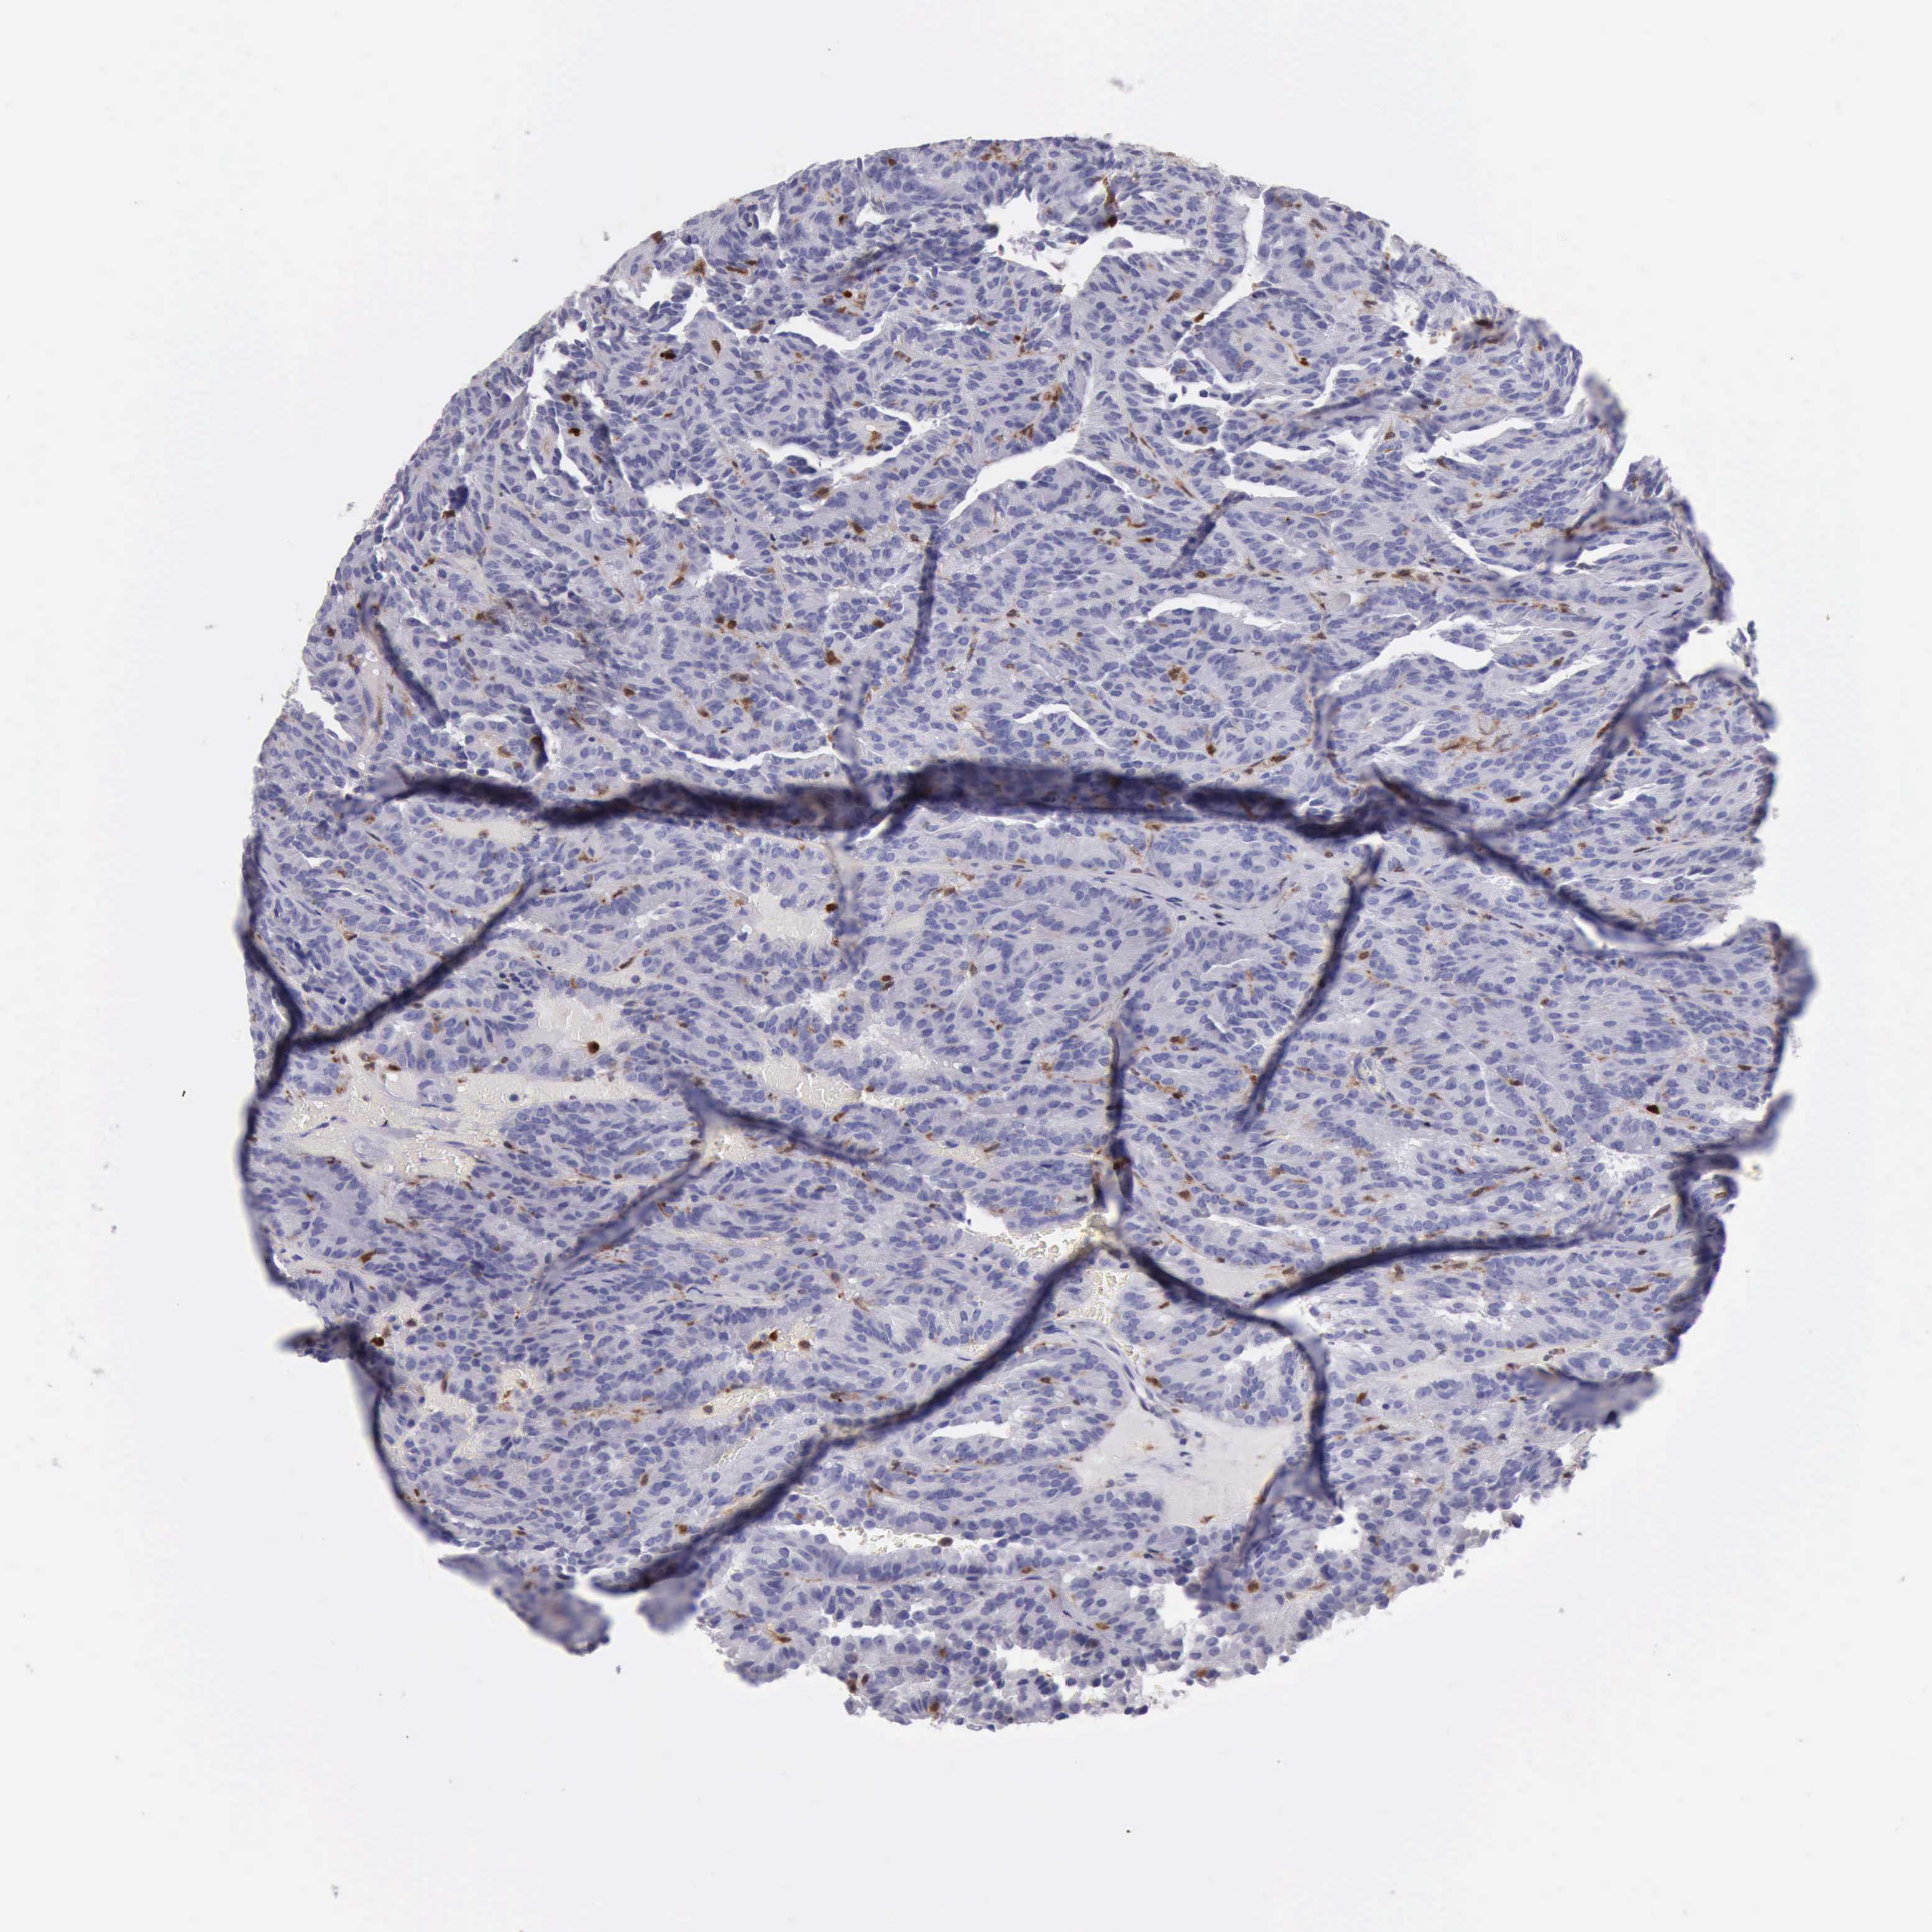

KIDNEY RENAL PAPILLARY CELL CARCINOMA (TCGA) - Interactive survival scatter ploti

The Survival Scatter plot shows the clinical status (i.e. dead or alive) for all individuals in the patient cohort, based on the same data that underlies the corresponding Kaplan-Meier plots. Patients that are alive at last time for follow-up are shown in blue and patients who have died during the study are shown in red.

The x-axis shows the expression levels (FPKM) of the investigated gene in the tumor tissue at the time of diagnosis. The y-axis shows the follow-up time after diagnosis (years). Both axes are complimented with kernel density curves demonstrating the data density over the axes. The top density plot shows the expression levels (FPKM) distribution among dead (red) and alive patients (blue). The right density plot shows the data density of the survived years of dead patients with high and low expression levels respectively, stratified using the cutoff indicated by the vertical dashed line through the Survival Scatter plot. This cutoff is automatically defined based on the FPKM cutoff that minimizes the p-score. The cutoff can be changed by dragging the vertical line or by entering a cutoff value in the square labeled "Current cut-off".

Under the Survival Scatter plot the p-score landscape (black curve; left axis) is shown together with dead median separation (red curve; right axis). Dead median separation is the difference in median mRNA expression between patients who have died with high and low expression, respectively. It is calculated as follows: median FPKM expression of dead patients with high expression - median FPKM expression of dead patients with low expression. This is intended to aid the user in visually exploring custom cutoffs and the associated p-scores and dead median separation.

Individual patient data is displayed and can be filtered by clicking on one or more of the category buttons on the top of the page. Categories describing expression level and patient information include: high, low, alive, dead, female, male and tumor stages. The scale of the x-axis can be toggled between linear and log-scale by clicking on the "x log" button. Mouse-over function shows TCGA ID, patient information and mRNA expression (FPKM) for each patient.

& Survival analysisi

Kaplan-Meier plots summarize results from analysis of correlation between mRNA expression level and patient survival. Patients were divided based on level of expression into one of the two groups "low" (under cut off) or "high" (over cut off). X-axis shows time for survival (years) and y-axis shows the probability of survival, where 1.0 corresponds to 100 percent.

CSTA is not prognostic in Kidney Renal Papillary Cell Carcinoma (TCGA)

Best expression cut offi

Based on the FPKM value of each gene, patients were classified into two groups and association between prognosis (survival) and gene expression (FPKM) was examined. The best expression cut-off refers the FPKM value that yields maximal difference with regard to survival between the two groups at the lowest log-rank P-value. Best expression cut-off was selected based on survival analysis .